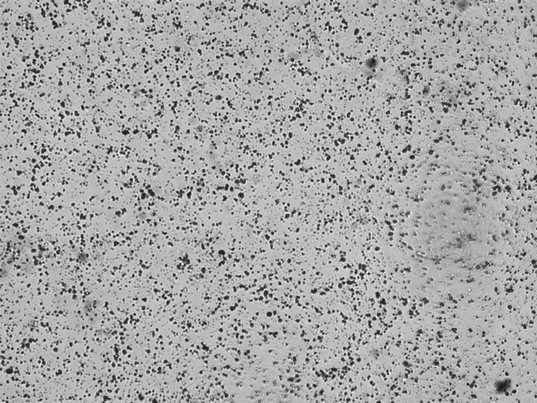

Während einfache Teststreifenanalysen nach wie vor ihren Platz in der Diagnostik haben, wird zunehmend auf automatisierte Verfahren zurückgegriffen. Diese ermöglichen es, große Mengen an Proben effizient zu analysieren und selbst kleinste Abweichungen zu erkennen. Diese neuen Technologien erleichtern die Arbeit im Labor, erfordern jedoch fundierte Kenntnisse, um die Ergebnisse korrekt interpretieren zu können. Die Befundung liegt bekannterweise nicht in den Händen der Labormitarbeiter – diese Kompetenz liegt bei den Ärzt*Innen. Die Aufgabe der Labormitarbeiter ist es aber, zu erkennen, um welche Bestandteile es sich im vorliegenden Harn handelt. Ein paar Fotos dieser Zellen werden hier nun gezeigt und benannt.

Unter diesem Text finden Sie ein paar Bilder eines Harnsediments. Um welche Zellen handelt es sich hier? Die Auflösung bekommen Sie in meinem elearning-Kurs.